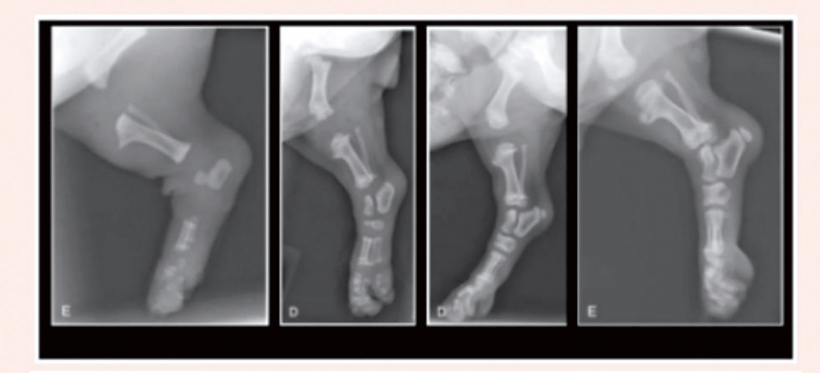

Kucēns, lai arī ir topošais medību suns, patiesībā ir ļoti viegli ievainojams, vārīgs radījums. Divu mēnešu vecumā tam joprojām nav izveidojušies cieti locītavu skrimšļi un viss ķermenītis turas kopā, pateicoties muskuļu un dzīslu spēkam. Tādēļ fiziskās aktivitātes nevar būt pārmērīgas.

Draudzējoties ar citiem suņiem, jāpielūko, lai kucēnu nevārta pa zemi, nepiespiež un, protams, nesakož. Nedrīkst ļaut lēkt no liela augstuma, kāpt pa trepēm.